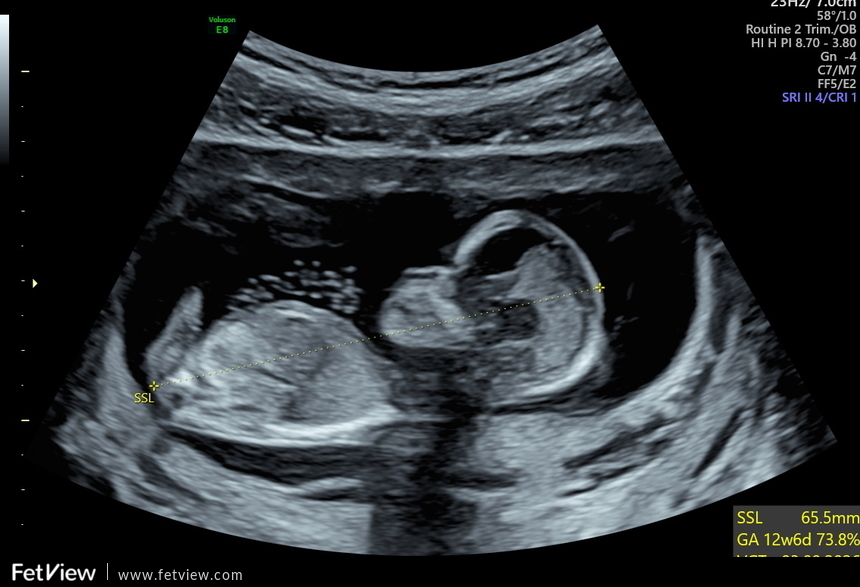

ich bin derzeit in der 13. SSW und hatte letzte Woche einen Ultraschall. Was meint ihr, kann man das Geschlecht erkennen? Der Arzt hatte eine klare Tendenz die er uns leider bisher nicht mitgeteilt hat. Ich kann leider nichts wirklich erkennen. Hier die Bilder aus 12+3. Vielen Dank fürs Miträtseln :)ip8o4cqlye7n.jpeg